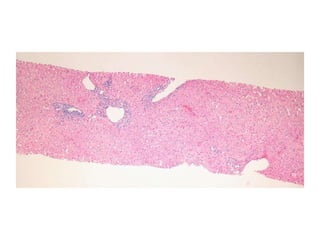

07-R-1192 Middle aged female with intractable pruritis.

S07-9238  Dx: Features compatible with primary biliary cirrhosis, Scheuer stage 1/4.

07-R-1192 Middle agedfemale with intractable pruritis.

S07-9238 Dx:Features compatible with primary biliary cirrhosis, Scheuer stage 1/4.